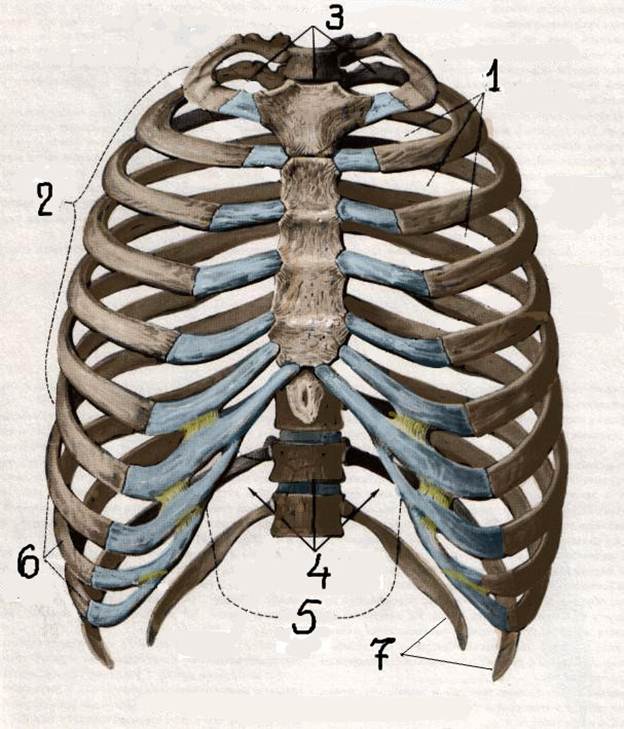

S: Цифрой 3 обозначена верхняя апертура грудной клетки (русский язык).